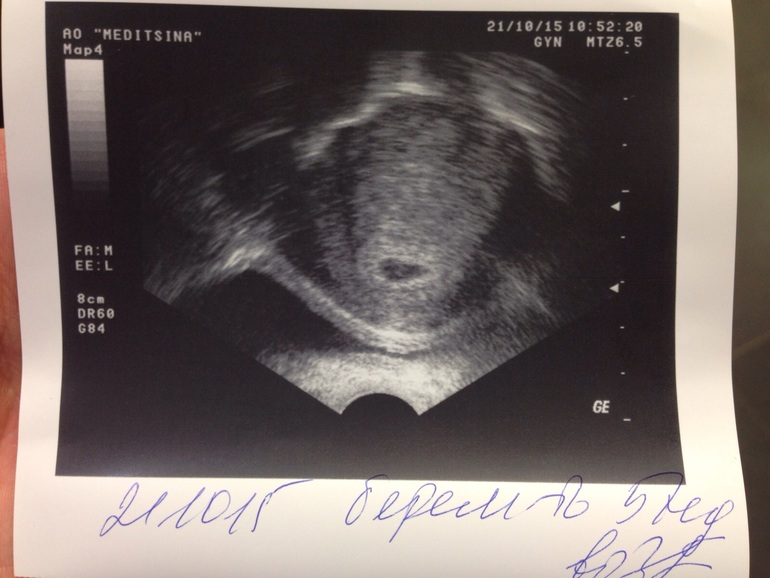

23 дпп пятидневок

23 дпп пятидневок 119 фотографий